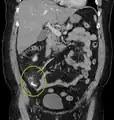

| A fecalith marked by the arrow which has resulted in acute appendicitis. | |

Appendicolith as seen on CT